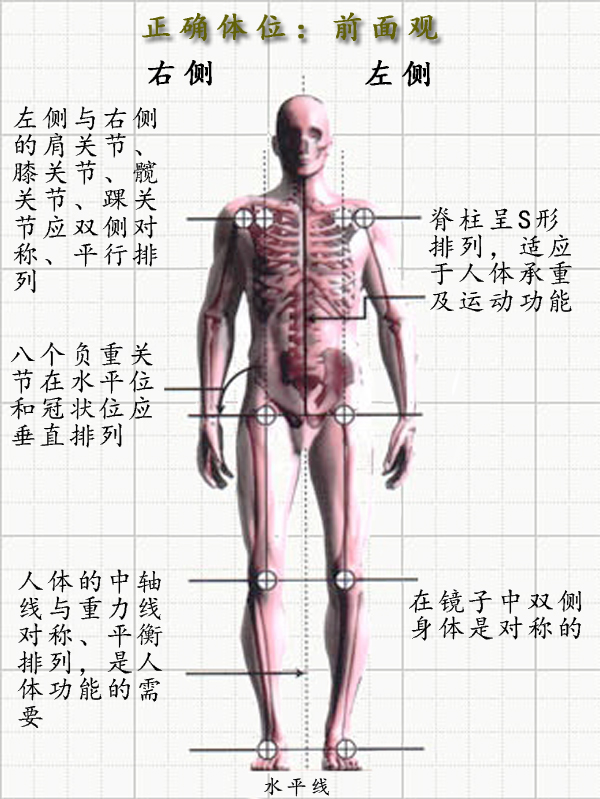

中立位的样子:

上图看上去没什么 感觉 ,对不对。

中立位

我们这里先说侧面看的体态中立位。如下图,如果我从天花板挂一个铅垂线,让线穿过你的脚一侧的外踝,体态好的人,线会穿过你的膝盖前 1 / 3 处,骨盆大转子,肩峰和耳垂。如果有任何的偏离,都基本说明体态出现了问题。

答案是有的,但我们所有人都不完美。对于大多数人来说, 良好的体态要求身体的各 部位 保持在正确的位置上,而不良体态往往可能导致 肌肉疼痛 , 关节活动 障碍,或是全身不适。传统意义上来讲,物 理疗 法、整骨、脊椎推拿疗法和目前的 瑜伽理疗 师,评估体态时,都是通过将 患者 的体态与正直的骨架进行比较而得。通过从背面、侧面、正面,观察客户身体各个部位如何有机结合,再与无性别的骨架的各部位结合状态作比较,得出结果。毫无意外,你会发现我们许多人的体态与 标准 骨架所展示的体态有很大的 区别 。

良好体态对于我们的帮助

更高效地使用身体

4、体态自我评估方法人的动作可以在三个动作面上进行,即矢状面、冠状面和 水平 面,如下图所示:

观察人的身体有 4 个角度:正面、背面和两个侧面,不同的角度观察的 内容 不同,也因此能发现不同的体态问题。

通过侧面观察,我们能发现自己在矢状面(前后) 的体态问题。正常状态下,人类 的身体中这五个点应该近似位于一条直线的:耳垂、肩峰、股骨大转子、股骨外髁、外踝。